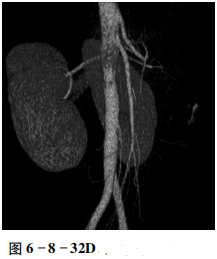

男性,22岁。间断肉眼血尿。CT检查结果如下:

增强扫描示肠系膜上动脉与腹主动脉之间的左肾静脉受压狭窄,狭窄后管腔扩张增粗(图6-8-32A、B),矢状位MIP示肠系膜上动脉与腹主动脉夹角约为15°(图6-8-32C),VR示肠系膜上动脉与腹主动脉夹角变小(图6-8-32D)。

肾静脉受压狭窄,肠系膜上动脉与腹主动脉夹角变小。

“胡桃夹”综合征。